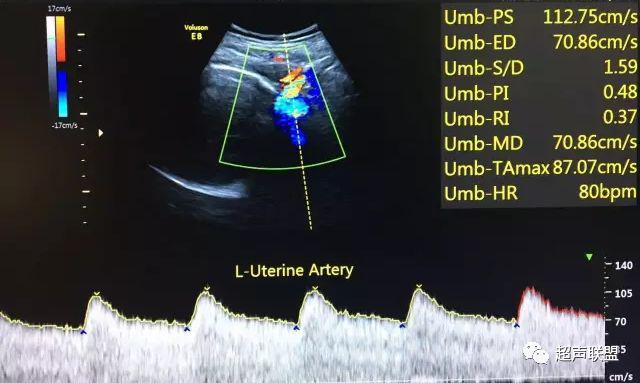

5 子宫动脉血流测定

正常妊娠时血流速度增加,血流阻力降落。缺氧早期的血流再分配,子宫动脉血流RI、PI值增加,阻力指数(RI)>0.57,子宫动脉血流频谱出现切迹。

3、子宫动脉标准:孕26或27周后,子宫动脉S/D>2.7,(RI)>0.57,有舒张早期切迹;

图7 正常中孕期子宫动脉频谱

图8 胎儿宫内缺氧,子宫动脉舒张早期可见切迹